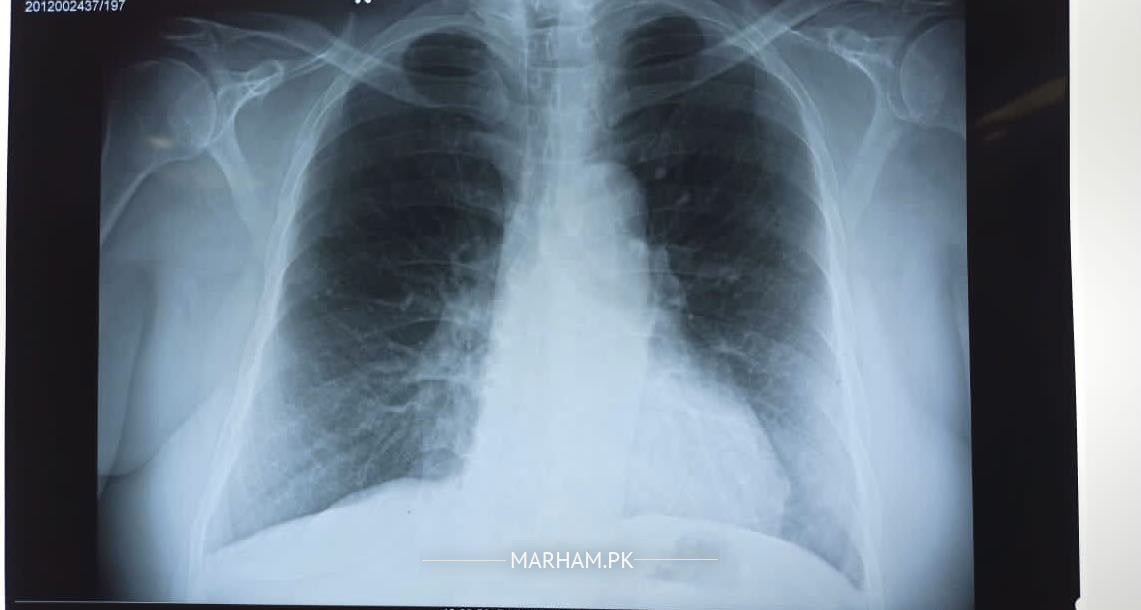

Patient developed symptoms 10 days ago with sore throat, a little fever on and off. Also having productive cough. COVID PCR was done 3 days ago with positive result. Oxygen saturation remains around 96-97. Attaching some xray and other tests requested. Please advise if any other action needed. current prescription attached. Previously before COVID test, he had been prescribed with Deltacort which is being continued by doctor till its full tenure